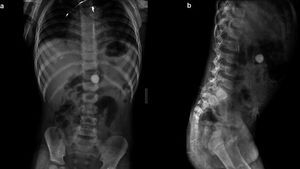

Foto-foto Rontgen Temuan Benda Aneh dalam Tubuh, Paku hingga Kawat Besi